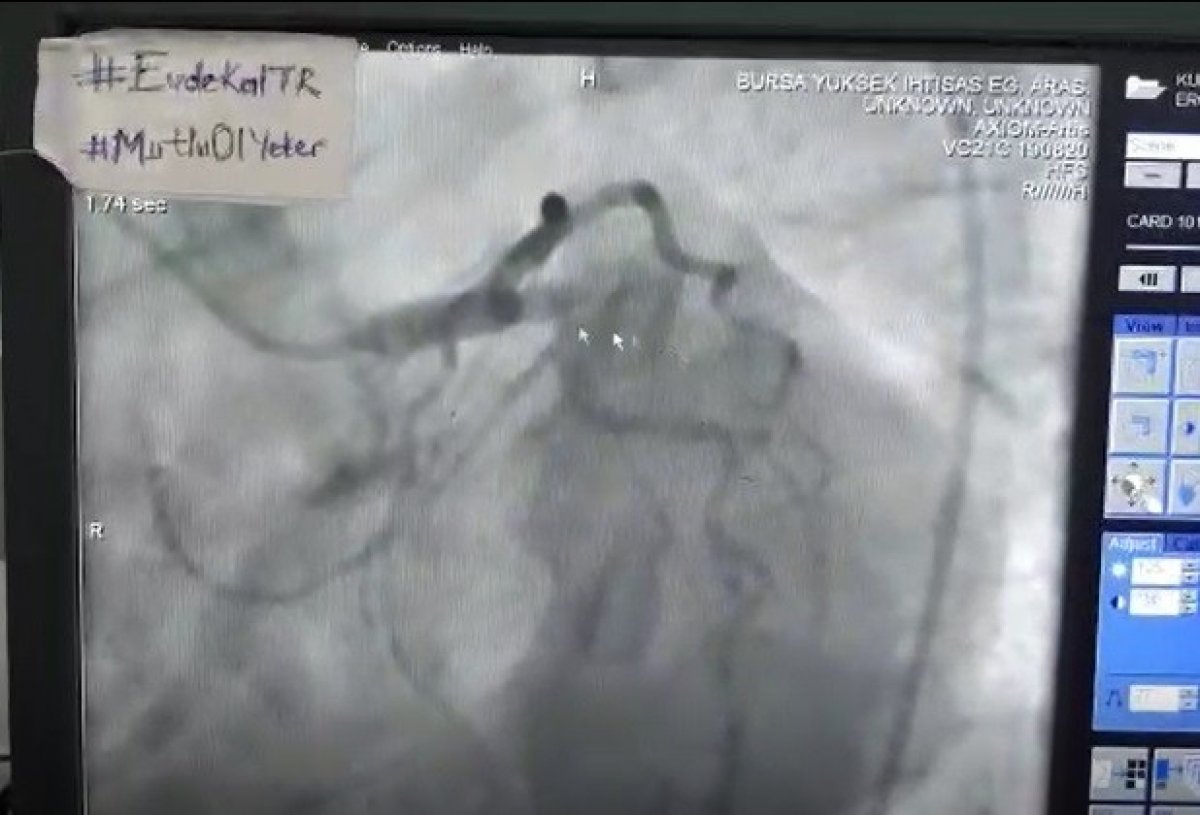

Bursa Yüksek İhtisas Eğitim ve Araştırma Hastanesinde koronavirüs testleri pozitif çıkan 58 yaşındaki bir adamın EKG sonuçlarından kalp krizi geçirdiğini belirleyen doktorlar, hastayı anjiyoya aldı.

Koronaya karşı tedbir alan doktor ekibi, hastanın kalbe giden tıkalı iki damarını balonla genişlettikten sonra stent takmayı başardı. Hasta 2 saat süren başarılı operasyonun ardından yeniden karantina odasına alındı.

Nadir görülen operasyonla ilgili konuşan Kardiyoloji Kliniğinde görevli Doç. Dr. Erhan Tenekecioğlu, "Bugün hastanemizde korona şüphesiyle yatmakta olan 58 yaşında erkek bir hastamızın serviste yatarken başlayan göğüs ağrılarının olması üzerine EKG’si çekildi. EKG’de hastanın akut kalp krizi geçirmekte olduğu tespit edildi. Bunun üzerine acilen anjiyo ve stent yapılması için hasta kliniğimize devredildi. Hastayı hemen anjiyografi ünitesine aldık. Biz de gerekli tedbiri aldık. Tulumlarımızı, maskelerimizi, gözlüklerimizi giyerek operasyona başladık. Hastanın anjiyosunda tam tıkalı olan damara telle ilerledikten sonra ince bir balon ile önce genişletme işlemi yaptık. Daha sonra tıkalı olan yere stentimizi gönderdik. Damarı açtıktan sonra ileride ikinci bir darlık olduğunu gördük. Oraya da ikinci bir stent takarak arada boşluk kalmaması için iki stentin birleşmesini sağladık. İşlemimizin sonunda hastanın damarı tam açıldı." diye konuştu.